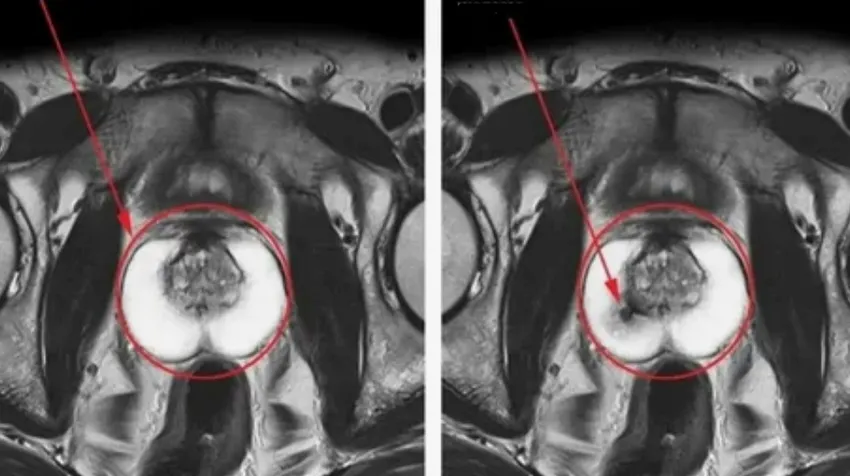

Так виглядає рак простати

Передміхурова залоза має складну систему кровообігу